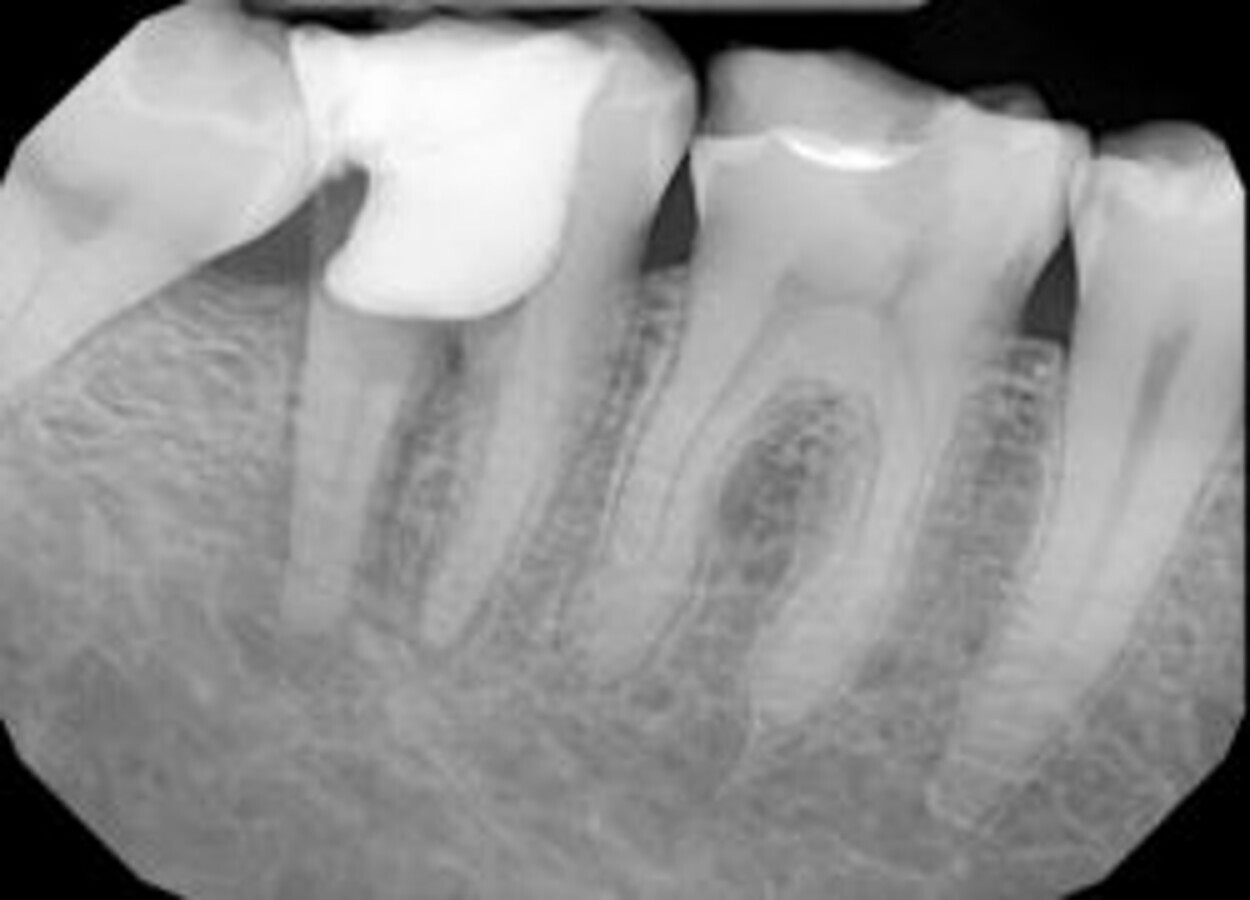

Pacijentkinja stara 36 godina poslata je u našu ordinaciju radi tretmana velike perforacije na zubu 46, u medijalnom i distalnom kanalu. Izvršeni su CBCT kao i RVG pregledi. CBCT je pokazao veliku sesiju koja perforira kost.

SLIKA 1